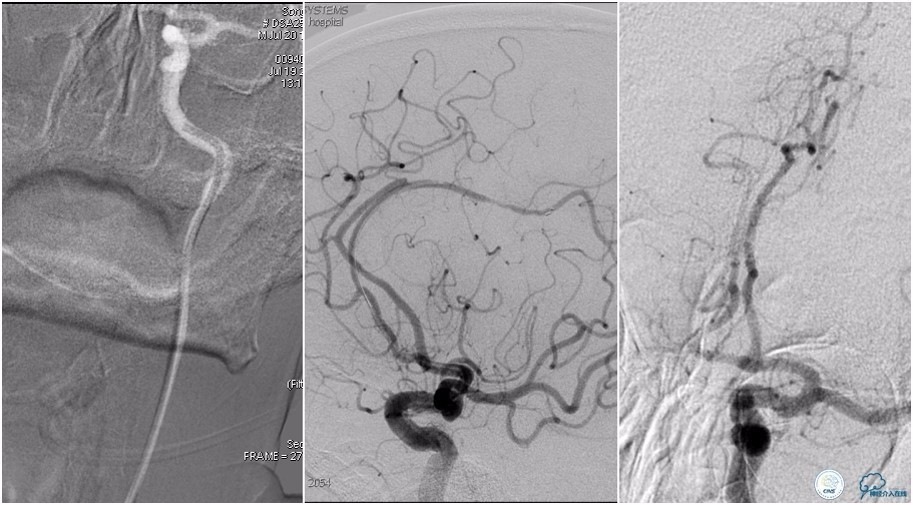

12:35穿刺成功,TOT 185min。3型主动脉弓,右侧颈内动脉起始部狭窄70%,右侧大脑前动脉A1段未显影。

双侧大脑前动脉A4段闭塞,右侧大脑前动脉由左侧大脑前动脉经前交通动脉代偿供血。

6F Envoy置于颈内动脉C3段,选用Solitaire-FR 4*20mm支架释放于右侧大脑前动脉,完全覆盖血栓。

6F Envoy置于左侧颈内动脉C3段,选用Solitaire-FR 4*20mm支架释放于右侧大脑前动脉取栓1次,血流达TICI 2b。

Solitaire-FR 4*20mm支架释放于左侧大脑前动脉取栓1次,取出少许血栓重复造影左侧大脑前动脉胼周动脉开口后,右侧大脑前动脉A2段以远未显影,考虑栓子逃逸。

选用Solitaire-FR 4*20mm支架分别于右侧大脑前动脉A2-A3段,左侧胼周动脉,右侧胼周动脉取栓3次。

双侧大脑前动脉完全显影,TICI 3级,TOR 261min。